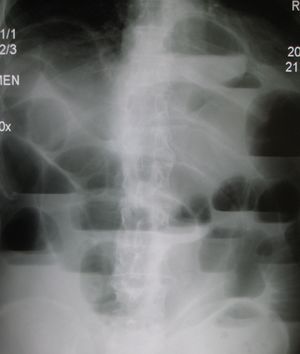

تتمثل أهم طرق التشخيص التي يمكن إجراؤها في حالة انسداد الأمعاء في اختبارات الدم أو عمل أشعة إكس على البطن أو الأشعة المقطعية و/أو أشعة الموجات فوق الصوتية. وإذا ما تم اكتشاف وجود ورم أو تكتل في الأمعاء، فقد يتم استئصال نسيج منه لتحليله وفحصه لمعرفة طبيعة هذا الورم أو التكتل.

من ضمن الأشياء التي يكشف عنها التصوير الإشعاعي وجود انتفاخ بالأمعاء ووجود مستويات متعددة (أكثر من ستة مستويات) من السوائل والغازات في صور الأشعة التي تؤخذ على البطن والمريض في وضع الاستلقاء على الظهر تارة والوقوف تارة أخرى.

وعلاوةً على ذلك، فمن الممكن استخدام حقنة الباريوم الشرجية أو صور أشعة ملونة للأمعاء الدقيقة أو الأشعة المقطعية لتحديد درجة انسداد الأمعاء، وما إذا كان الانسداد جزئيًا أم كليًا، وكذلك لمعرفة سبب الانسداد.